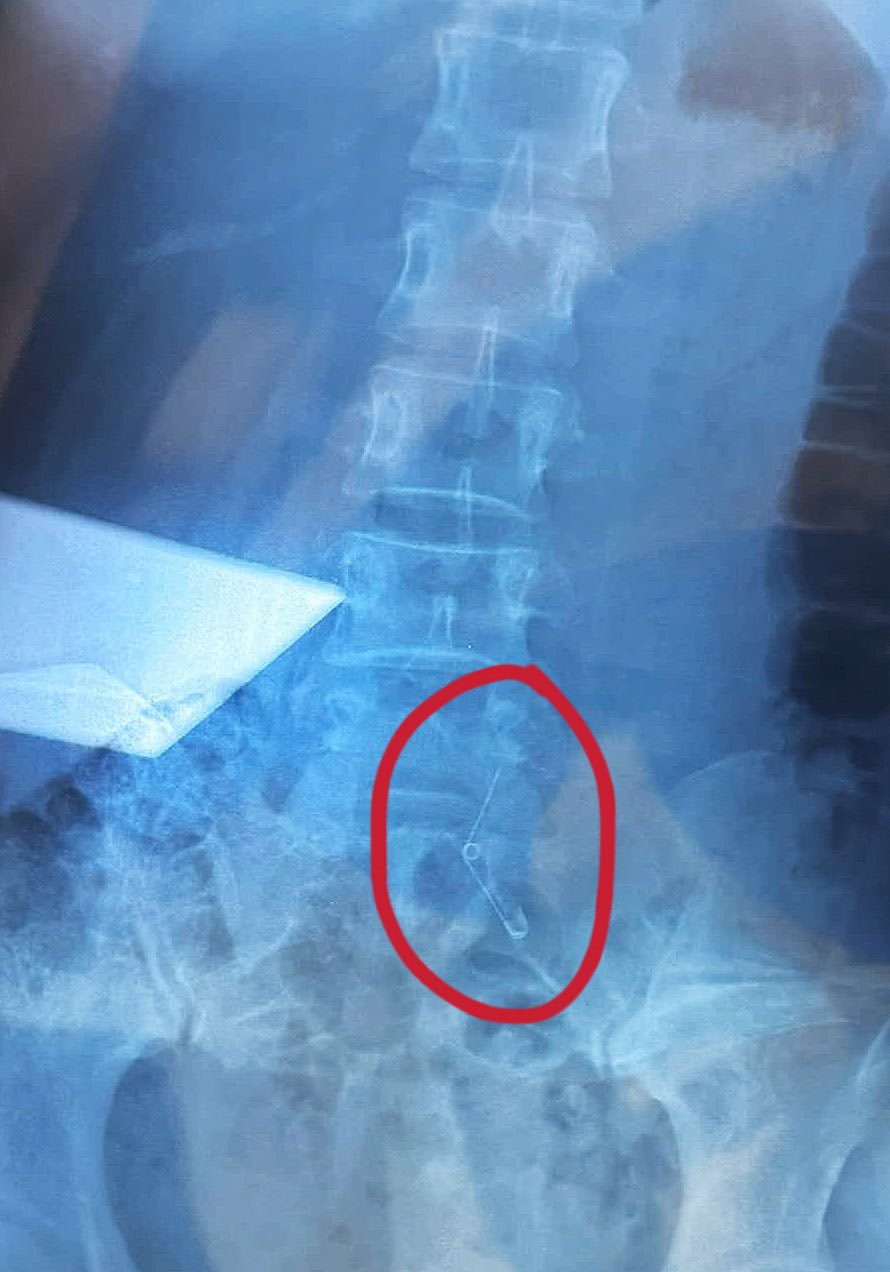

Theo đó, vào tối 26/9, Vân Anh cùng nhân viên công ty ở TP.HCM đi ăn ốc. Đang ăn, cô cảm thấy nuốt nghẹn nghẹn và nhận ra mình không còn cầm kim băng – vật dùng để khều ốc trên tay nữa. Sau đó Vân Anh được đưa đi cấp cứu và mất 6 tiếng để mổ lấy kim băng ra.

Ở phần bình luận cô giải thích thêm rằng vì không nội soi thực quản được nên bác sĩ quyết định mổ. Hiện tại, tình hình của cô đã ổn định hơn, đáp lời hỏi thăm của mọi người: “Ăn ốc 2 triệu, tìm kim 70 triệu”.